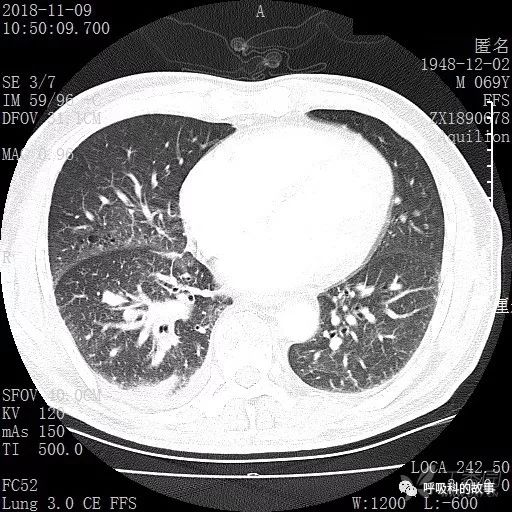

胸部增强CT示右肺门占位伴远端阻塞性肺炎,纵膈、右肺门、右侧颈根部、右侧腋下及肝门部肿大淋巴结。两侧胸腔少量积液。

肺窗CT

2018/11/16 气管镜检查报告: 气管镜经鼻进入顺利, 声门闭合可, 气管环清晰, 隆突锐利: 右上叶支气管及右中间支气管见纵行皱襞, 右中叶及右下 叶背段支气管粘膜肿胀, 管腔狭窄, 气管镜无法进入, 右下叶基底段支气管口粘膜肿胀, 管腔狭窄, 气管镜无法进入, 管口见少许白色坏死物突出管腔。 于右下叶基底灌洗, 活检, 刷检找脱落细胞、 结核菌及液基细胞学检查。2018/11/20 病理-常规检查报告: (右下叶基底段管口) 少量粘膜慢性炎伴上皮鳞化, 其内见嗜酸性粒细胞浸润,另见炎性肉芽组织, 试做酶标及特染。免疫组化结果:CK(上皮+) 特殊染色结果:抗酸(-),六氨银(-)。病理-液基细胞检查报告: (淋巴结) 穿刺: 见坏死组织及少量淋巴细胞,。